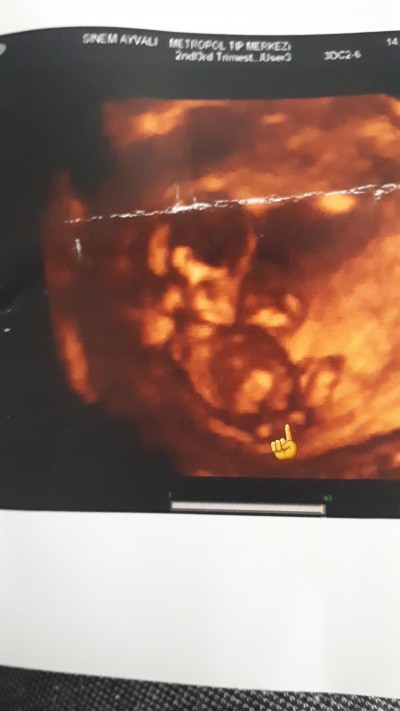

Kızlar ya doktora gittim bugn yine doktor sürekli cıkıntı var erkege benziyor diyor ama bisey diyemem diyo tecrübeli olanlar resime bakarak nolur soylermisiniz cok  merak ediyorum 2.cocugum şurda okla gosterdiğim yer top gibi onami diyor acaba çıkıntı diye

Orta parmak :D Valla sanki de erkeğe benziyor